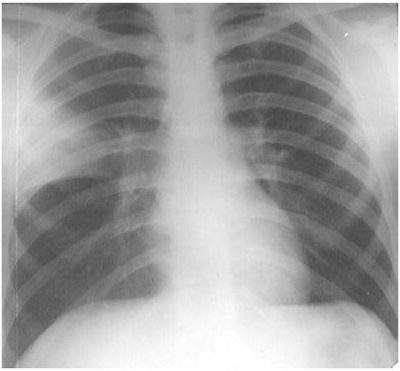

Question

Revalida - 2014 Um paciente com 24 anos de idade, estudante universitário, procura Unidade Básica de Saúde referindo há dois dias “febre alta”, de início súbito, dor torácica na inspiração profunda e tosse produtiva, com expectoração amarelada. Nega antecedentes patológicos significativos. Ao exame o paciente apresenta-se lúcido, orientado, com mucosas normocoradas, normo-hidratadas, escleróticas anictéricas. Aparelho respiratório: murmúrio vesicular audível, exceto em terço médio de hemitórax direito, onde ausculta-se um sopro tubário. Verifica-se aumento do frêmito tóraco-vocal nessa mesma região. Aparelho cardiovascular: ritmo cardíaco regular em dois tempos com bulhas normofonéticas, sem sopros. Abdome flácido, ausência de visceromegalias. Membros inferiores sem alterações. Sinais vitais: pressão arterial = 120 × 80 mmHg, frequência respiratória = 24 irpm, frequência cardíaca = 98 bpm e temperatura axilar = 39,0 ºC. A radiografia de tórax realizada no atendimento é mostrada abaixo. A conduta terapêutica mais adequada para essa paciente é

Answer

• cefalexina por via oral.

• azitromicina por via oral.

• levofloxacina por via oral ou endovenosa.

• ceftriaxona endovenosa ou intramuscular + azitromicina por via oral.